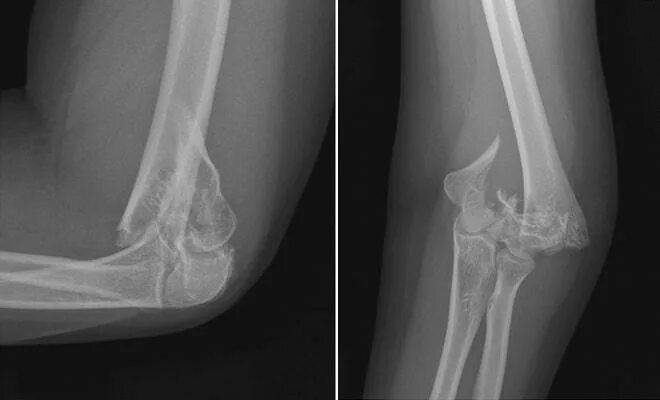

Перелом локтевой сустав мкб 10